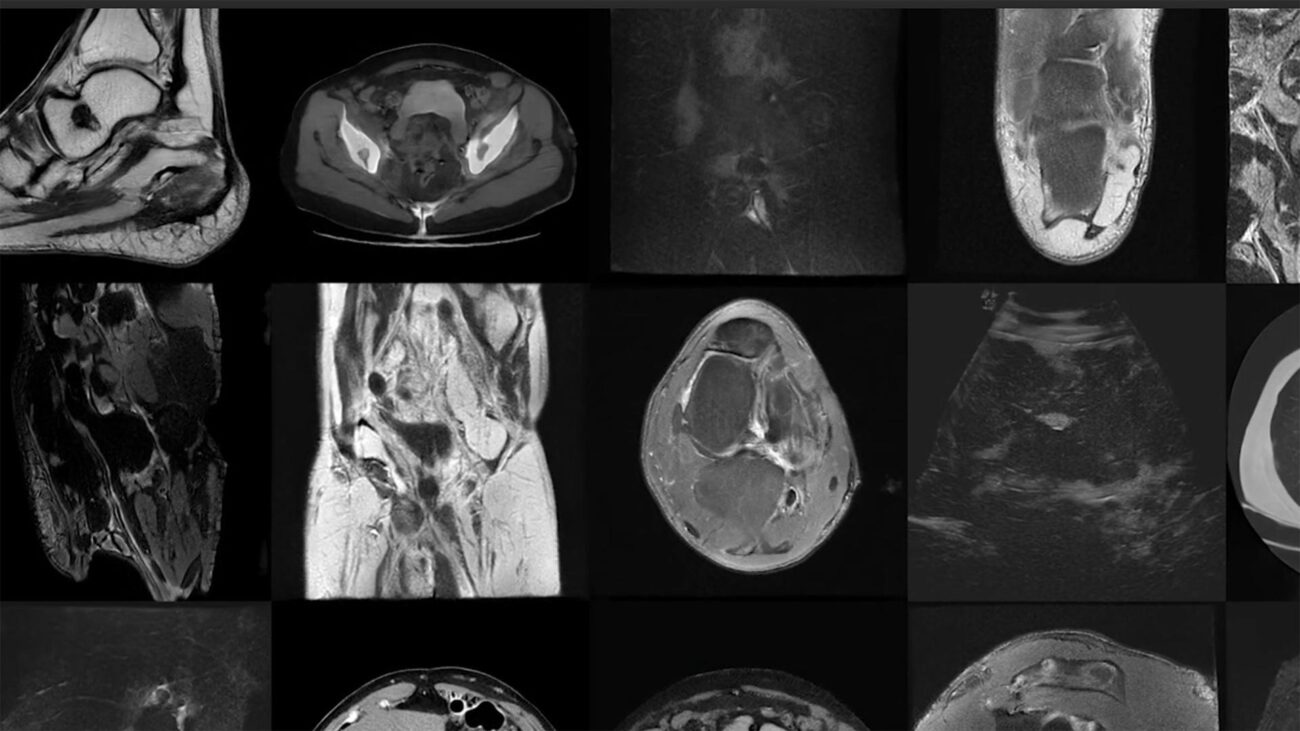

Manejo del dolor en pacientes geriátricos con aneurisma aórtico.

El manejo del dolor en pacientes geriátricos con aneurisma aórtico es crucial para mejorar su calidad de vida. Es importante utilizar estrategias multimodales y personalizadas para proporcionar alivio y confort, teniendo en cuenta las necesidades específicas de cada individuo.